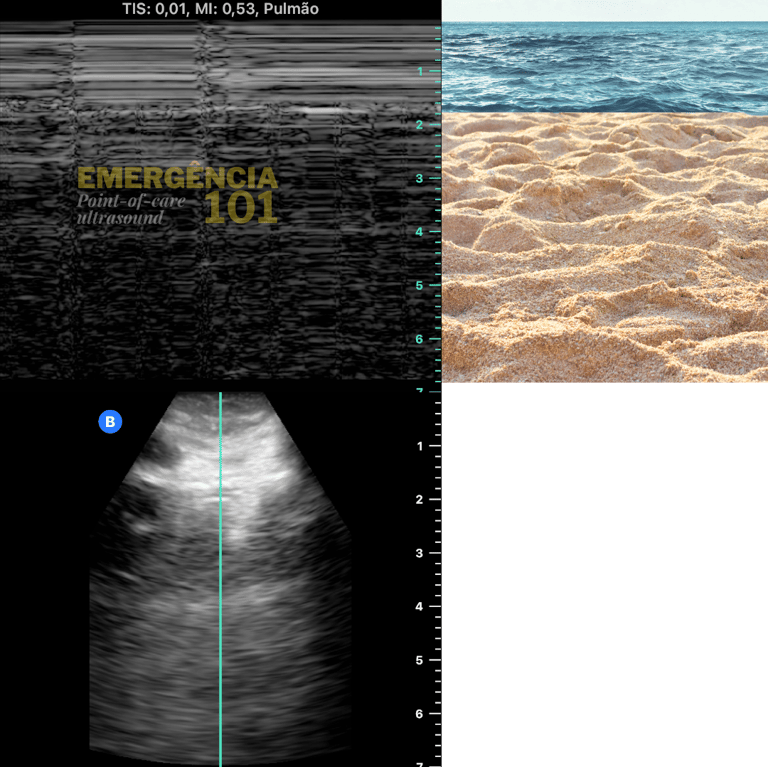

Em algumas situações, pode ser difícil visualizar se há ou não deslizamento pleural pelo modo B do ultrassom, como na avaliação dos ápices pulmonares, que são regiões naturalmente menos ventiladas, e/ou em pacientes com movimentos respiratórios menos intensos (imagine um paciente intubado com sedação profunda e volume corrente pequeno), nesses casos é possível utilizar o modo M (motion) do ultrassom para registrar o movimento da pleura, gerando dois sinais característicos:

Sinal da areia da praia: presença de deslizamento pleural. (figura 7b)

Sinal do código de barras: ausência de deslizamento pleural. (figura 7c)

Figura 7b. Seashore sign (Sinal da areia da praia no modo M), significando presença de deslizamento pleural no campo pulmonar avaliado. Acervo pessoal do autor.

Figura 7c. Barcode sign (Sinal do código de barras no modo M), significando ausência de deslizamento pleural no campo pulmonar avaliado, não necessariamente causado por pneumotórax. Acervo pessoal do autor.